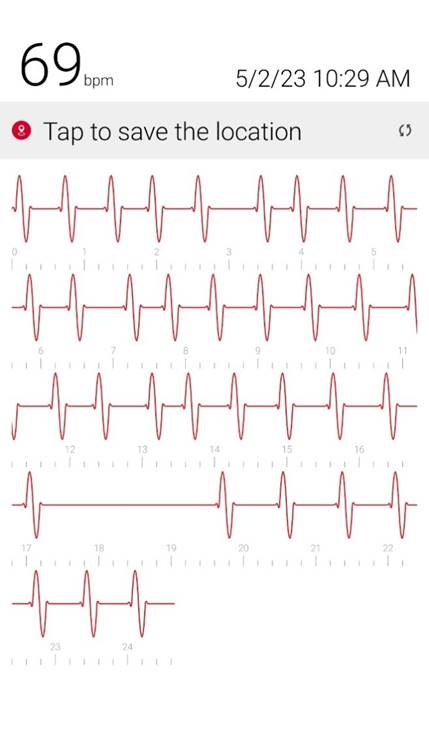

Initial ID consult diagnosed local tetanus based on clinical symptoms and recommended oral Metronidazole 500mg every 6 hours as an outpatient. Autonomic involvement developed with tachycardia and cardiac arrhythmia, along with episodes of sudden sweating. Loud noises made twitching/spasms worsen. Intermittent twitching continued to be present bilaterally in the body, face, jaw & tongue. Symptoms were suppressible with benzodiazepine. Tetanus IM IG 500 IU was recommended and obtained. After initial 2 week course of metronidazole was discontinued symptoms worsened again when patient would walk. Multiple trials of oral Metronidazole 500mg every 6 hours were attempted with some improvement while on the antibiotic but then return and worsening of symptoms again once antibiotic was discontinued.

incrementally, then once twitching had reached the spinal level, muscle twitching spread to the bilateral muscles of the body with cardiac arrhythmia & autonomic involvement/ sweating. A trial of antibiotic Keflex (cephalexin ) was suggested, which only at high dose (1000mg PO every 6 hours), helped keep spasms localized to the left foot mostly but symptoms would worsen and generalize if antibiotic Keflex (cephalexin) was stopped for more than 2 days. Benzodiazepine was increased to every q6 hours to reduce muscle twitching that had become constant in the left foot. Symptoms improve when patient does not walk or avoids any pressure or bending of left big toe and symptoms worsen when patient walks or stops antibiotic and has been unable to stop antibiotic for the past year and a half without worsening of symptoms. When antibiotic is stopped for 2 days bilateral jaws begin to snap shut intermittently involuntarily and cardiac arrhythmia/ heart block reoccurs. Symptoms worsen further after 4 days off antibiotic. Local

Oral Keflex (cephalexin) 1000mg 4 times a day & IM Bicillin LA 2.4 million units 3 times a week were restarted with improvement in bilateral body muscle twitching but twitching / spasms locally in the left toes and foot continued. This regimen was continued for 7 weeks. One day after discontinuing oral Keflex (cephalexin) (and 3 days after the last bicillin IM shot) spasms again began at the left big toe, left toes and left foot, progressed up the left leg to the left gluteal muscles and again once the spinal level was reached spasms spread to the right side of the body and then upper body and by 1 and 1/2 days after all antibiotic was discontinued, arrhythmia/heart block began again. Oral Keflex 1000mg 4 times a day was restarted (cephalexin). Benzodiazepines had been continued throughout.

3) Cardiac Arrhythmia / Heart Block occurs during generalizations

When antibiotic is discontinued or with increased walking, rhythm returns to normal when antibiotic is restarted after a few days.